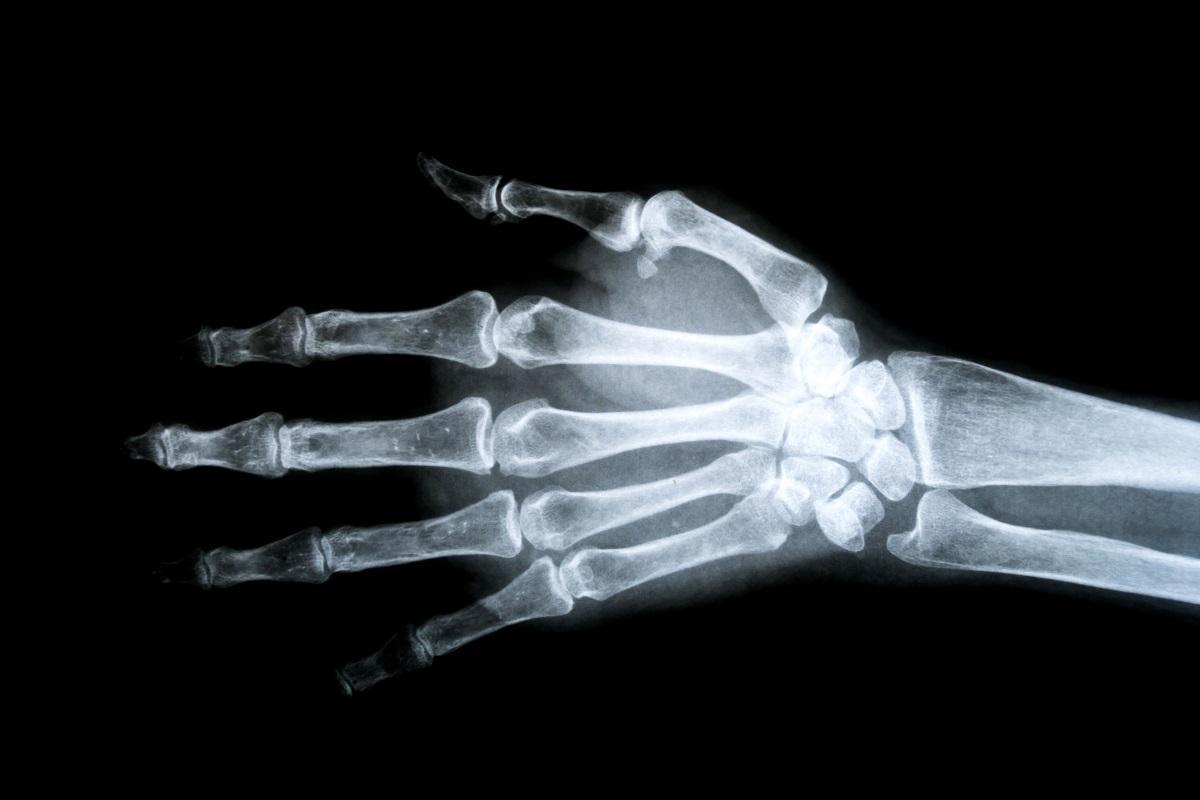

¿En qué consiste la rotura del ligamento escafolunar? / Adobe Stock.

Hemos oído muchas veces hablar de que a alguien se le había ‘abierto la muñeca’. En realidad, detrás de esta expresión lo que hay es una rotura del ligamento escafolunar, lo que el doctor Alejandro Almoguera, especialista en mano del Departamento de Cirugía Ortopédica y Traumatología de la Clínica Universidad de Navarra, considera una lesión común en la muñeca provocada por caídas con la mano extendida.